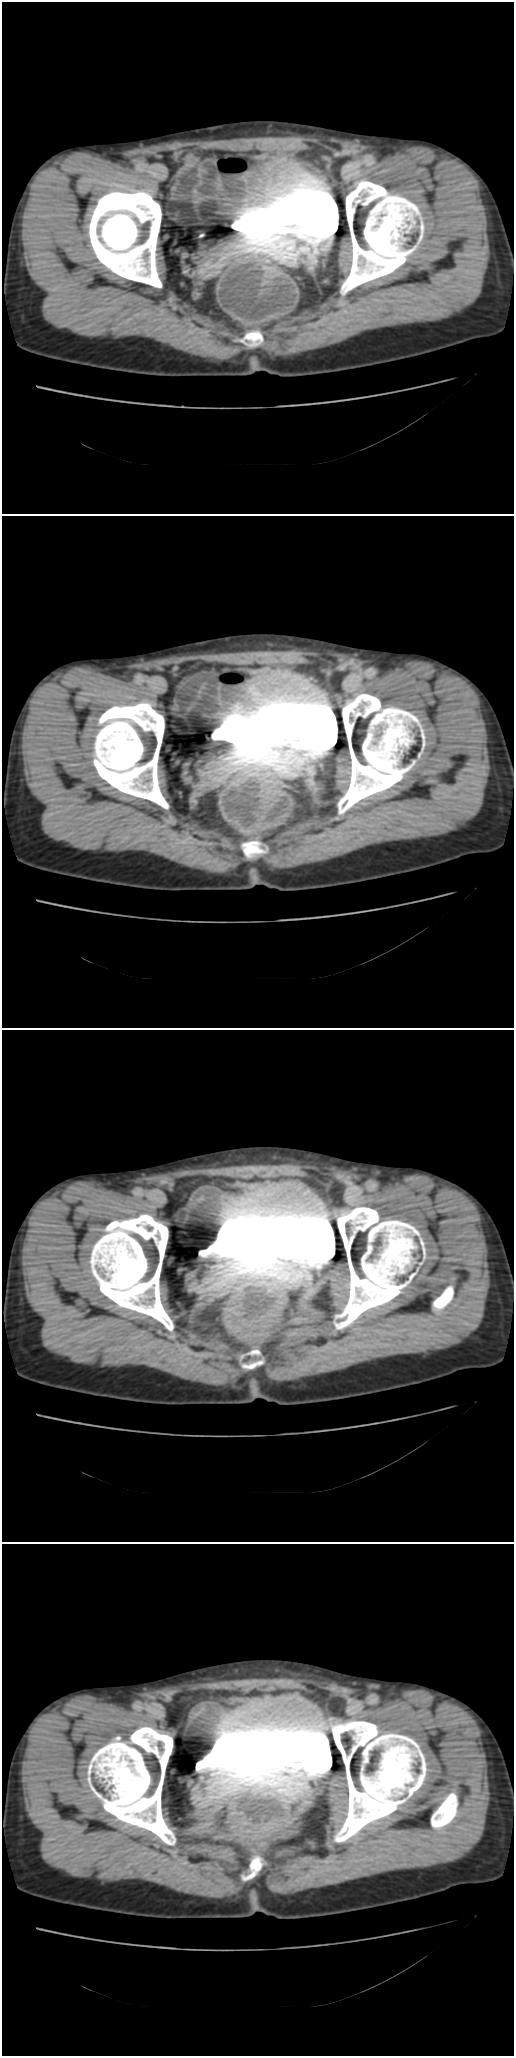

该病人今天做了增强,右侧髂骨病灶明显强化。

临床和影像学表现:女性患者46岁,有子宫肌瘤手术病史。影像所见可见残余宫颈部分,左右附件未见新生物;右髂骨翼后端囊状膨胀性骨破坏,囊性部分感觉有强化(楼主标上增强前后的ct值就很好了),未见明确的液—液平面,周边硬化不明显或轻度硬化。

分析:患者年龄46岁,没有明确外伤病史,病变呈膨胀性骨破坏,囊性部分未见明确的液—液平面,周边硬化不明显。综合分析该病例比较符合骨巨细胞瘤,不太符合动脉瘤样骨囊肿。

诊断:1、首先考虑骨巨细胞瘤;2子宫肌瘤术后改变